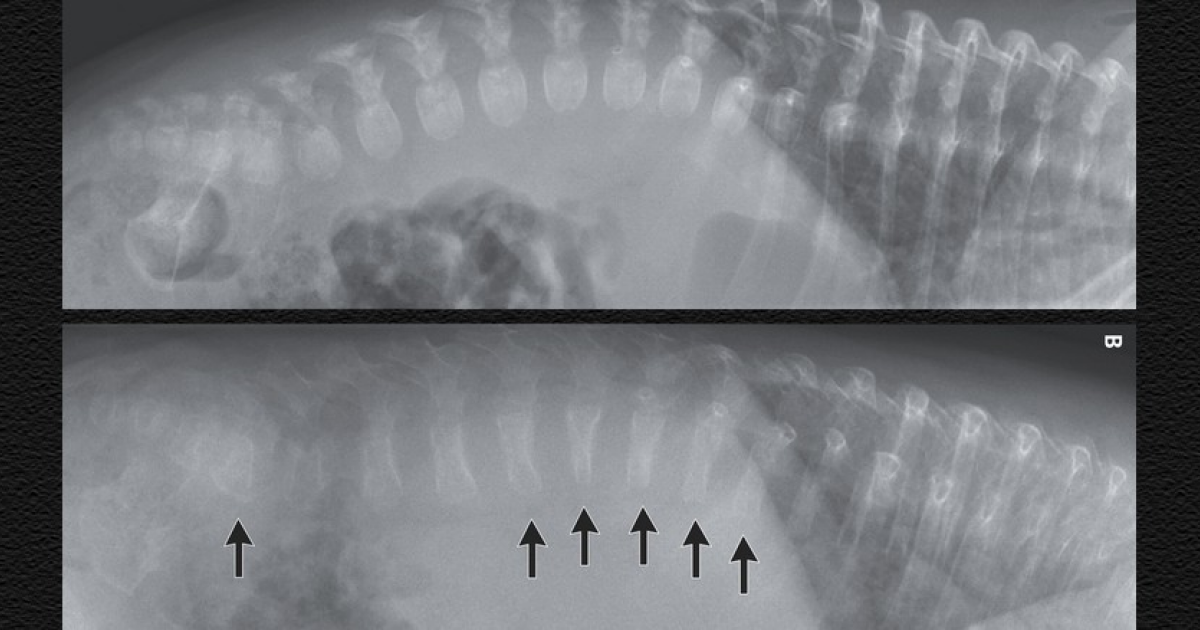

Немецкие врачи помогли младенцу с несовершенным остеогенезом. Немецкие врачи помогли младенцу с несовершенным остеогенезом